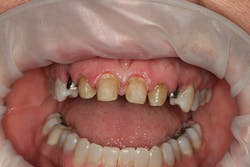

A 32-year-old white female presented for a cosmetic consultation. The patient reported that during her teenage years she had received orthodontic treatment to move her permanent maxillary canines mesially into the spaces that should have been occupied by her congenitally missing lateral incisors. She stated that her dentist, orthodontist, and oral surgeon had decided to place endosseous implants in the canine spaces due to the greater availability of bone in comparison to the bone available in the lateral positions (figure 1). As she grew older, she had become increasingly dissatisfied with the appearance of her smile and was seeking a more updated and esthetic solution (figure 2).

Figure 1